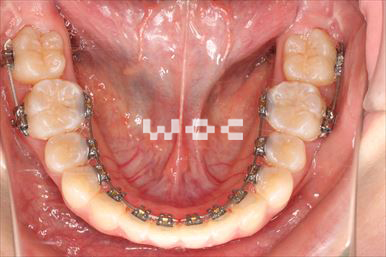

出っ歯舌側矯正

上下舌側矯正を希望。

通院状況や歯みがきの協力が良かったため、1年7ヶ月で治療を終えることができました。※装置と注意事項に関しては、大人の矯正装置一覧へ。

- 年齢:20歳女性

- 主訴:出っ歯が気になる

- 基本矯正料金:120万円

- 治療期間:1年7ヶ月

- 抜歯部位:上顎両側第一小臼歯